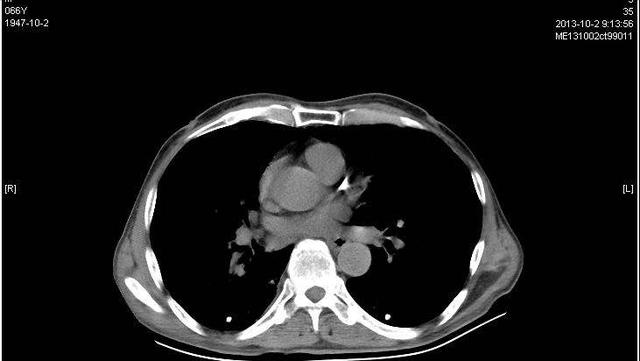

肺石灰化病巣は、高齢者、特に結核の既往のある患者に多くみられる。 結核治療後の画像検査で石灰化陰影がみられることがある。

肺石灰化症が肺結節と合併している場合、肺結節は悪性または良性の可能性があり、大きさ、位置、成長速度、形態に基づいて判断されるため、異なる見方が必要である。

実際、石灰化病巣は有害ではないが、結節を伴う場合は注意が必要で、特に悪性の場合は積極的に治療に協力しなければならない。